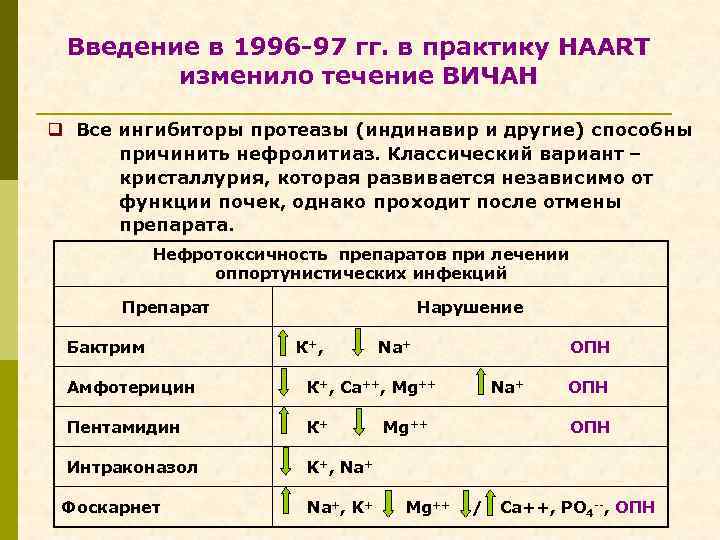

Введение в 1996 -97 гг. в практику HAART изменило течение ВИЧАН q Все ингибиторы протеазы (индинавир и другие) способны причинить нефролитиаз. Классический вариант – кристаллурия, которая развивается независимо от функции почек, однако проходит после отмены препарата. Нефротоксичность препаратов при лечении оппортунистических инфекций Препарат Бактрим Нарушение К+, Na+ Амфотерицин К+, Са++, Mg++ Пентамидин К+ Интраконазол ОПН K+, Na+ Фоскарнет Na+, K+ Na+ Mg++ ОПН / Ca++, PO 4 --, ОПН